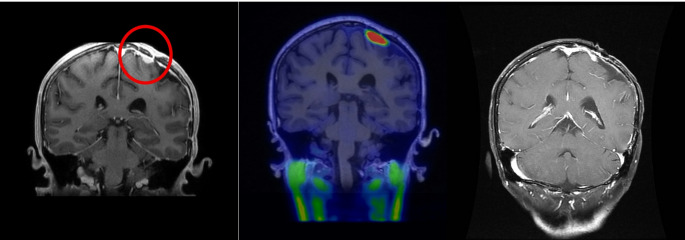

Methods: We retrospectively analyzed 13 patients with recurrent meningiomas treated with salvage BNCT at the Tsing Hua Open-Pool Reactor between August 2020 and May 2024. Tumor uptake was assessed using either ¹⁸F-BPA or ¹⁸F-Fluciclovine PET. Treatment response was evaluated using RANO criteria, and outcomes were analyzed in relation to dosimetric and clinical factors.

Results: Of the 13 patients (1 WHO grade 3, 6 grade 2, and 6 grade 1), 5 (38%) responded to BNCT. Responders had significantly higher tumor mean dose (45.10 vs. 25.85 GyE, p = 0.003). Tumor location influenced dosimetry; non-skull base tumors received higher doses and showed a trend toward better response. TNR and tumor size were not predictive of response. No severe adverse events were observed.